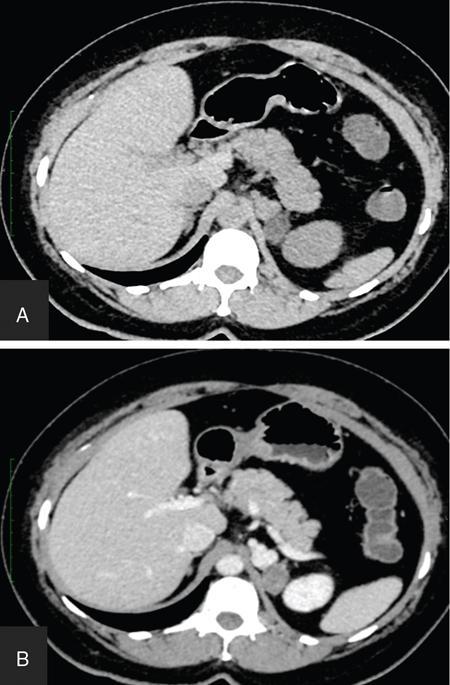

ADRENAL ANATOMY AND IMAGING TECHNIQUES Dipak Patel, Sanjay Mehta, Vishal Shah The adrenal glands (also called suprarenal/surrenal glands) are a pair of endocrine glands, retroperitoneal in location, situated superior and ventromedial to kidney on either side. Bartolomeo Eustachi described regrading adrenal in 1563 while its importance was recognized by Thomas Addison in 1855 and Brown-Séquard in 1856. It has two distinct components, the cortex and medulla, responsible for the production, release of the multiple hormones, regulating the metabolism, salt–water equilibrium in blood stream and immune system functions; besides helping body’s response to stress. Adrenal has two main parts: the cortex and the medulla. It is enclosed in complete fibrous capsule, merging with the renal capsule on either side and liver on right side. Because of lipid rich contents, cortex appears yellow. It consists of three microscopic zones. Zona glomerulosa – outer most layer, produces mineralocorticoids, largely responsible for the regulation of blood pressure; zona fasciculata – central layer, responsible for the production of glucocorticoids and zona reticularis – inner zone, thinner and darker, produces androgens. Medulla is the core of the adrenal, surrounded by the cortex and mainly found in head of the gland. It is ellipsoid in shape, grey-tan in colour and <10% of the gland volume. Greatly vascularized medulla emanates about 80% of adrenaline (epinephrine) and 20% noradrenaline (norepinephrine) (Fig. 10.16.1.1). Computed tomography (CT) histogram is another tool to unenhanced CT. It utilizes Hounsfield unit (HU) of each pixel in the given region in context of its number as well as frequency of negative pixels. It has been noted that >10% negative pixel (i.e. less than 0 HU correlate with the amount of lipid content) on histogram has sensitivity of 91% to detect adenomas accurately as compared to sensitivity of 66% on unenhanced CT scan, if used alone. Dedicated multiphasic adrenal CT protocol consists of unenhanced phase, followed by venous (about 60–90 s, after intravenous injection of nonionic iodinated contrast about 1.3–1.5 mL/kg body weight at the rate of 3–4 mL/s) and delayed (at 15 min) phases. Routinely neutral oral contrast is preferred unless indicated otherwise. Acquisition of additional arterial phase images (20–25 s) may be considered for two reasons, one for understanding adrenal arterial anatomy, may provide a guide for surgical mapping, if needed, and another to see for any hypervascular lesion like pheochromocytoma. Adrenal washout ratios are obtained using venous and delayed contrast images. (Venous and delayed phase images are required for the calculation of adrenal washout ratios.) For the evaluation of HU values, ROIs have to be placed covering at least two-thirds of the lesion, excluding areas of calcification, necrosis or haemorrhage, if any. Absolute washout = Enhanced density − Delayed density (HU) Enhanced density − Unenhanced density (HU) × 100% Relative washout = Enhanced density − Delayed density (HU) Enhanced density (HU) × 100 % Accuracy of washout calculation improves after the incorporation of unenhanced HU value (inclusion of noncontrast HU value helps in more accurate calculation of washout); therefore, whenever possible, absolute percentage wash-out (APW) should be calculated. Absolute and relative washout of about ≥60% and ≥40%, respectively, strongly suggest benign adrenal adenoma. There are certain pitfalls to washout ratios, ROI calculation may be inappropriate if it is a heterogeneous lesion with haemorrhage/necrosis and few of the lesions may show similar enhancement characteristics (hypervascular adrenal metastases, pheochromocytomas and adrenocortical carcinoma). Certain technical modifications can be applied to reduce the radiation dose and scan time, like higher pitch (should not be more than 1.5 for optimal image quality). Low-dose CT scan (LDCT) is performed with kilovoltage peak (kVp) in the range of 90–120 and mA of 40–80, particularly for lung cancer screening. According to Godoy et al., adrenal masses >2 cm (or ≥1 cm in patients with cancer history) and <4 cm in LDCT should be evaluated with adrenal protocol CT. Dual-energy CT scan (DECT) uses two different tube voltages in a single acquisition, like 140 and 80 kVp. Postcontrast and excretory phase acquisition will be done at two different tube current in single breath hold. Virtual noncontrast images have been acquired after subtraction/deduction of iodine from the contrast images. With this data set, we can calculate the contrast washout values and diagnose adenoma. Magnetic resonance imaging is a second preferred imaging modalities for assessment of adrenal disease. It has the advantage of multiparametricity, multiplanarability and high contrast-to-noise (CNR) compared to the CT scan. Chemical shift imaging (CSI) furnishes details of microscopic fat (CSI provides insight into intracytoplasmic fat). The normal adrenal appears isointense to the renal cortex on T1-weighted images and may show corticomedullary differentiation on T2-weighted images. Standard magnetic resonance imaging (MRI) protocol should provide information about the anatomical and histological characteristics of an adrenal mass (Table 10.16.1.1). Fluid component of lesion is appreciated on T2-weighted images. Pheochromocytoma appears hyperintense compared to other lesions. Diffusion-weighted images (DWIs) – Apparent diffusion coefficient (ADC) value of adenoma and metastatic lesion show considerable overlap in their values, which limits the use of DWI in the indeterminate lesion. Pheochromocytoma reveals high ADC value than adrenal metastasis or adenoma. Postcontrast dynamic imaging is useful in case of indeterminate lesion where contrast study provides information regarding enhancement pattern and vascularity of lesion. Same parameter is mandatory for the enhancement evaluation of lesion on precontrast and postcontrast studies. A dynamic study has been acquired in arterial, interstitial and delayed phases using breath-hold 3D gradient sequences. CSI is the most important tool to detect microscopic fat and hence in the differentiation of adenoma with other lesions. We will discuss about fundamental principles behind CSI in short as it has been covered in detail in the section of MRI physics. Roles of CSI would be described in different section. High intracytoplasmic (microscopic) fat is one of the features of adrenal adenoma. Fat-suppressed MR sequences are sensitive to detect macroscopic fat, but CSI due to its virtue to detect microscopic fat becomes a mainstay for adrenal MRI. Chemical shift manifests differences of Larmor frequency in protons and shown in parts per million (ppm). The chemical shift for fat and water is 3.3–3.5 ppm. In-phase and out-phase imaging is commonly used in clinical practice for chemical shift. Latterly, Dixon methods are widely applied for CSI. Phase cancellation artefact happened because of chemical shift is exploited for in-phase and out-phase imaging. When protons of fat and water are in-phase (same location), the received signal from protons are additive while fat and water protons are completely in out-phase, the received signals cancel each other. The Dixon method is acquired using the same principle of in-phase and out-phase imaging and then fat and water imaging created by mathematic postprocessing. Fat-water swapping – measurement fallacy occurred in areas of field inhomogeneity leads to error in deciding voxel contents of water or fat. So, fat- and water-only images may not be useful. Black boundary artefact or Indian ink artefact is seen at the interface of water and fat, usually seen at muscle–fat interface and the boundary of abdominal organ, which will be the hallmark to identify out phase images. Adrenal lesion characterization better performed by conventional in-phase and out-phase images while quantitative assessment of fat in adrenal lesion better accomplished on Dixon technique. Qualitative assessment is the visual analysis for signal drop between in-phase and out-phase images of adjacent organs like liver, spleen or paraspinal muscles. Subtraction images show a signal drop at a bright spot, which makes identification of fat within the lesion more obvious. Quantitative assessment is the process in which ROI kept on in-phase and out-phase images of lesion to acquire signal drop. Fat fraction and fat ratio are additional quantitative methods to measures fat in the lesion by Dixon techniques. The fat fraction is the proportion of fat signal of lesion on fat-only images divided by sum of lesion signal intensity on fat- and water-only images. The fat ratio is the value which show signal intensity of lesion on fat-only images compared to anterior abdominal wall subcutaneous fat signal intensity on fat-only images. Spleen is preferred as a reference organ as propensity of fatty infiltration into liver and paraspinal muscle. In case of iron deposition in the spleen, kidney parenchyma can be used as a reference organ. Microscopic fat within tissue makes them appear darker on out-phase images than in-phase images. Four sets of images: water-only, fat-only, in-phase and opposed-phase are the result of a Dixon sequence. Microscopic fat has been detected and quantify by this technique. Indeterminate lesions on plain CT with density higher than 10 HU and less than 30 HU further evaluated with the help of contrast-enhanced CT with adrenal protocol which exploits washout characteristics of lesion or chemical shit MRI which identifies signal dropout due to abundance of microscopic fat within the lesion. Embryonic origin of adrenal cortex is from mesoderm while medulla is from neuroectoderm. Outer cortex further divides into three distinct layers, which already we understood in anatomic section. Adrenal primordium develops by the 25th day of gestation, medial to the mesonephros and urogenital ridge. Adrenal gland enlarges to 1 mg by the 45th day of gestation. Medulla develops by the migration of primitive sympathetic cells and neural crest at around 45th day. At about 18th week of gestation, foetal adrenal is four times the kidney and it weighs around 5 gm at birth, about one-third the size of kidney as a result of regression in size of the cortex. Adult-type cortex is developed by 4–5 years of age. Adrenal agenesis has association with ipsilateral renal agenesis while fusion of adrenal glands (joining posterior to abdominal aorta) has association with fused kidneys. Adrenal hypoplasia occurs as absence/hypoplasia of the foetal cortex with deformed medulla or as disorganized foetal medulla and cortex with absent permanent cortex. Ectopic location of adrenal is called adrenal heterotopia. Congenital adrenal hyperplasia leads to early puberty in boy and girl and appearance of male characteristics in female due to impaired production of cortisol and raised levels of male hormones. The adrenals, retroperitoneal structures lie ventromedial and superior to the kidneys and enclosed by the perirenal fascia. Each glands made of body and medial and lateral limbs. Right adrenal appears as ‘V’ or comma shape and left adrenal appears as ‘Y’ or triangular shape. Right adrenal is comparatively smaller than the left gland. Maximum width of the right adrenal is about, 6.1 mm and of left adrenal 7.9 mm. Normal weight is 4–6 gm. Relations — Right adrenal show right crus of diaphragm and right inferior phrenic artery medially, laterally right lobe of liver, anteriorly inferior vena cava and posteriorly right kidney. Left adrenal has left crus of diaphragm and left inferior phrenic artery medially, anteriorly splenic vessels, pancreas, lesser sac and stomach, anteromedially diaphragm and posteriorly left kidney. Three pairs of arteries supply adrenal glands, superior adrenal artery, which is a branch of inferior phrenic artery; middle adrenal artery, a branch of abdominal aorta and inferior adrenal artery, a branch of renal artery. Venous drainage – Right adrenal vein is short and drains into IVC and left adrenal vein is longer and drains into left renal vein. Lymphatics are limited to the capsule only and drain into the para-aortic nodes. Celiac, aorticorenal and renal ganglia supply postsynaptic fibres and abdominopelvic splanchnic nerves supply presynaptic fibres to the gland. Imaging of adrenal is indicated for differentiation of benign versus malignant lesions, nonmetastatic versus metastatic lesion and hence to reach up to definite diagnosis, to avoid invasive procedures or follow-up. Medullary tumour like pheochromocytoma and occasionally neuroblastoma are better evaluated on nuclear scan. Adrenal lesion evaluation done by different imaging modalities which includes ultrasound, CT, MRI and nuclear imaging. Adrenal glands are often difficult to see on ultrasound, and hence not the imaging modality of choice. However, ventrolateral axial scanning is the best approach to assess the adrenals. Ultrasound is the choice of investigation for the evaluation of adrenals in neonate and young children, which will be dealt within paediatric section. CT is one of the baseline imaging modality for the evaluation of adrenal lesions. On detection of incidental or suspected adrenal lesion, protocol should be tailored for optimum characterization of adrenal pathology. Due to widespread use of multidetector CT, number of adrenal incidentalomas is increased. Adrenals appear as inverted ‘V’-/‘Y’-shaped organs, situated ventromedial and superior to the kidneys. Scanty retroperitoneal fat may render imaging of adrenals difficult due to compromised spatial resolution. Unenhanced CT and multiphase contrast-enhanced CT play a very important role in adrenal imaging. On noncontrast (unenhanced) CT, evidence of intralesional macroscopic fat is highly suggestive of benign myelolipoma, whereas CT density of <10 HU suggests benign lipid rich adrenal adenoma and hence further imaging is not required. It also helps to evaluate foci of intralesional haemorrhage as well as calcification. ADRENAL INCIDENTALOMA Rushabh Shah Adrenal incidentalomas or incidental adrenal lesions are defined as clinically inapparent adrenal masses or nodules (larger than 1 cm) discovered incidentally during diagnostic imaging performed for indications other than adrenal disease. Probability of adrenal incidentalomas increases with age approximately 0.2% in young age reaches up to 7% to 10% in old age. Adrenal incidentalomas further subclassified into nonfunctioning versus functioning, primary versus metastatic, benign versus metastatic. Most frequent (80% to 90%) type of the incidentaloma is nonfunctioning benign adenoma. However, adrenal gland is the common site for metastasis and much less commonly site for primary adrenal tumours including pheochromocytoma, functioning adenomas and adrenocortical tumours (Tables 10.16.2.1–10.16.2.2). Adenoma (nonfunctioning) Adenoma (functioning) – cortisol secreting, aldosterone secreting Hyperplasia (PBMAH – primary bilateral macronodular adrenal hyperplasia) Adrenocortical carcinoma (secreting or nonsecreting) Pheochromocytoma (benign/malignant) Ganglioneuroma Neuroblastoma, ganglioneuroblastoma Haemangioma, angiosarcoma myelolipoma – lipoma, teratoma and other mesenchymal lesions More commonly from lung, breast, ovarian, kidney, melanoma, lymphoma, leukaemia Endothelial, pseudocyst, epithelial, parasitic, hamartomatous Lymphoma, amyloidosis, sarcoidosis Tuberculosis, histoplasmosis, blastomycosis The primary role of imaging in management of incidentalomas is to correctly identify hyperfunctioning adenomas and relatively uncommon malignant lesions and as a result avoiding unnecessary clinical workup – follow-up of benign clinically and radiologically insignificant disease. In 2017, American College of Radiology (ACR) incident finding committee published a white paper regarding management of incidental adrenal lesions. Recommendation takes into consideration of certain diagnostic features (presence of macroscopic fat, low CT density – less than +10 HU, signal drop on chemical shift imaging and presence of haemorrhage). Further lesions with large size or growing size have been considered as suspicious. History of known malignancy or clinical signs and symptoms related functioning adrenal lesion may help in management of incidental adrenal lesions for metastasis or functioning adrenal tumours, respectively (Fig. 10.16.2.1). ADENOMA Bhavdeep Rabadiya One of the most common benign adrenal cortical neoplasm, adrenal adenoma, depending on hormone secretions classified into ‘hyperfunctioning’ and ‘nonhyperfunctioning’. A precursor for hormone production is believed to be intracytoplasmic fat in adrenal cortex. Intracytoplasmic fat is seen in about 70% adenomas, which are lipid-rich and substantial amounts of lipids is not seen in lipid poor 30% adenomas. Nonhyperfunctioning and even few hyperfunctioning adenomas are clinically silent and they are frequently discovered as an incidentaloma. Adrenal adenomas are usually made up of cell cords with intracytoplasmic lipid. Significant association between functional status and lipid content of adenomas is not still established. Differentiation between hyperfunctioning and nonhyperfunctioning adenomas is not yet established by chemical shift (CS) magnetic resonance imaging (MRI). Nonhyperfunctioning adenomas are the most common adrenal tumour, approximately 70% of total adrenal masses and greater than 90% of incidentalomas. These lesions are clinically nonsignificant, but may require characterization in order to exclude other causes of an adrenal mass. Due to the absence of ionizing radiation as seen on computed tomography (CT), MRI is modality of choice for following up. Precontrast and postcontrast CT scans with delayed phase can also diagnose adrenal cortical adenomas. Cortisol producing adenomas are common hyperfunctioning adrenocortical neoplasm. Cushing’s syndrome is a complex resulting from excess levels of cortisol due to either endogenous causes or prolonged steroid administration. Excessive production of adrenocorticotropic hormone (ACTH) by pituitary adenoma is known to cause 85% of endogenous Cushing’s syndrome (Cushing’s disease). Contrast-enhanced MRI brain, focused on sella/pituitary gland helps in determining pituitary adenoma. About 15% of endogenous, Cushing’s syndrome is ACTH-independent, where the cortisol production is autonomous. About 50% of these lesions are probably due to adrenocortical neoplasm, commonly an adenoma, than carcinoma. Hyperaldosteronism, may be suspected of for patients who present with hypokalaemia or persistent hypertension despite conventional therapy. About 60% of primary hyperaldosteronism, is caused by an aldosterone-producing adenoma, which is also called ‘aldosteronoma’, described first by Conn. Forty per cent of cases are idiopathic. Aetiology of sex hormone-producing adenomas is either central or peripheral. Lesions secrete androgens oestrogens, which cause virilization or feminization. It results in sexual precocity, hirsutism, gynecomastia or impotence. Rapid progression of symptoms suggests a neoplastic source of hormones, and ovaries and adrenal glands should be evaluated. Adenomas are usually small, homogeneous, having well-defined margins and measure less than 3 cm. Morphologic features overlap with malignant lesions. Adenomas are characterized by the presence of intracytoplasmic fat. And to differentiate adenomas from malignant lesions, a high level of specificity is recommended. CT densitometry (HU) may be used to distinguish nonadenomatous lesions from adenomas. More than 50% surface area of the lesion needs to be covered by region of interest (ROI) for densitometry. A cut-off value of <10 HU is conventionally used to identify an adenoma on noncontrast-enhanced, CT scan (Figs. 10.16.3.1 and 10.16.3.2). Noncontrast-enhanced CT scan and chemical shift imaging (CSI) have limitations in the evaluation of lipid poor adenoma, which are 30% of total adenomas. Differentiation between lipid-rich and lipid-poor adenomas may be possible in delayed enhancement in CT (HU values). Adenomas de-enhance faster than nonadenomatous lesions. There is delayed and persistent contrast accumulation in malignant adrenal pathology due to increased vascular density and increased permeability due to disorganized angiogenesis. Percentage washout calculation gives reproducible method to evaluate contrast washout and to identify the adrenal lesion. Absolute and relative percentage washout (APW and RPW, respectively) formulae are described in various imaging techniques. For reasonably accurate calculation of washout, noncontrast HU value needs to be included; therefore, if possible, APW should be calculated. APW of >60% and RPW of >40% highly suggests adenoma. If the precontrast-enhanced HU value indicates benignity, then it should supersede the washout characteristics. Lesion with noncontrast enhancement value of ≥43 HU might raise high suspicion for malignancy regardless of washout characteristics. Adenomas appear isointense to hypointense on T1-weighted image, isointense to mildly hyperintense on T2-weighted image demonstrates less enhancement and shows rapid washout than pheochromocytoma or adrenal metastases. CSI with in-phase and opposed-phase gradient-echo sequences so far the best imaging technique, which depend on intracellular lipid content of adenoma (Fig. 10.16.3.3).